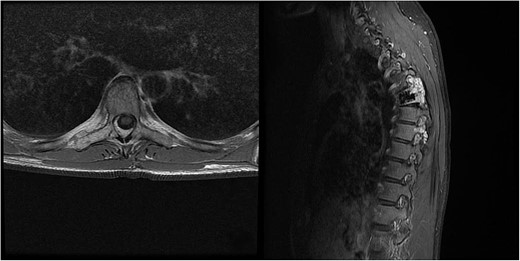

We decided to perform a revision total en bloc spondylectomy at Th6, along with resection of the Th8 pedicle and costovertebral joint, with a partial resection of the adjacent rib. Posterior spinal fixation from Th3 to Th10 was performed using radiolucent carbon screws, and the Th6 body was reconstructed using a radiolucent expandable cage (Figs 3 and 4). During the surgery, MEPs and SEPs were lost, with the patient waking up paraplegic (ASIA score B, VAS pain score 5). Immediate postoperative MRI showed no residual signs of thoracic spinal cord compression due to tumour or haemathoma (Fig. 5). The patient’s neurological status substantially improved the day after surgery, and thereafter, gradually improving over the next few days, allowing the patient to walk independently within 10 days (ASIA score D, VAS pain score 3). A multidisciplinary council decided against postoperative radiotherapy to avoid aggravating neurological symptoms by possibly causing additional damage to the myelopathic spinal cord. On the 11th postoperative day, the patient reported dyspnoea, and urgent CT angiography revealed peripheral pulmonary embolism, which was managed utilizing Deltaparine. Subsequent postoperative course was uneventful, leading to his discharge on the 15th postoperative day, ambulating independently using a walker. MRI follow-up was conducted 6 months postsurgery, followed by yearly checks. At the last follow-up, 2.5 years after the second surgery, there were no signs of tumour recurrence, and the patient exhibited no gait disturbance, back pain, or radiological signs of spinal instability (Fig. 6) (ASIA score E, VAS pain score 0).

Immediate postoperative MRI showing no residual signs of thoracic spinal cord compression.